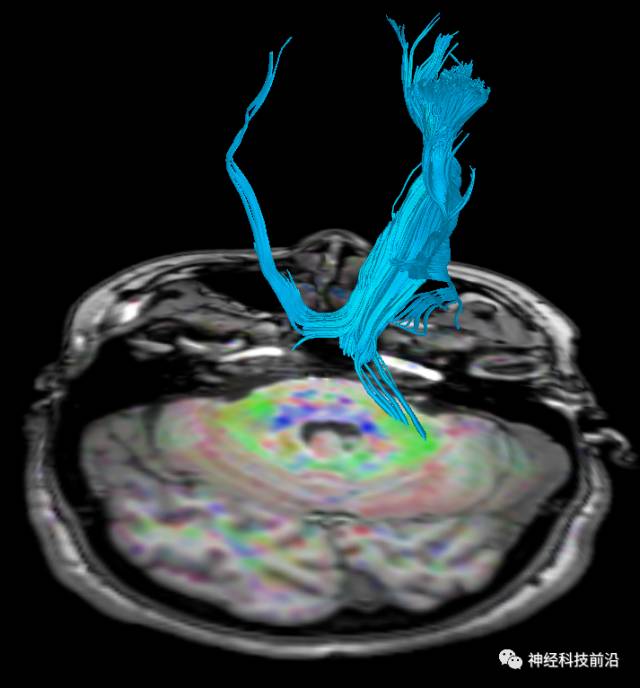

下面为皮质脊髓束的走形及位置